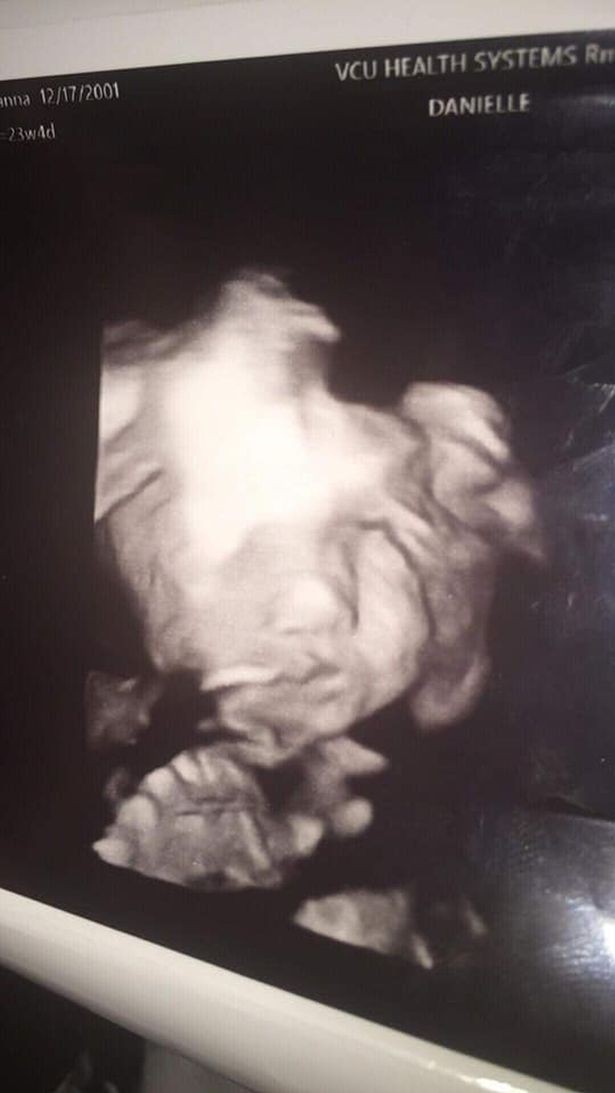

Một bà mẹ trẻ dù khá là sốc khi nhìn thấy hình ảnh đứa con gái mở to mắt, nở nụ cười bí hiểm nhìn chằm chằm về phía mình trong lúc siêu âm thai nhi 24 tuần tuổi khiến bà mẹ hết hồn, nhưng cũng yên tâm phần nào khi bác sĩ thông báo bé phát triển khỏe mạnh và bình thường.

Trong lần siêu âm thai nhi 24 tuần tuổi mới đây, cô Iyanna Carrington, tới từ Richmond, bang Virginia, Mỹ không chỉ cảm thấy hồi hộp mà còn có chút sốc khi thấy mặt con mình.

Bà bầu này kể lại: "Trong lần siêu âm này, tôi sẽ biết giới tính của con. Lúc đầu họ chiếu mặt đứa bé thì bình thường, y tá cho biết đây là một bé gái. Sau đó họ chiếu lại mặt đứa bé một lần nữa thì có cảnh tượng này, con gái cứ nhìn thẳng về phía tôi như thế. Tôi nói 'nhìn bé như một bóng ma' ngay giữa phòng và bác sĩ đáp lại thản nhiên 'Ừ, chuyện này cũng bình thường thôi mà'.".

Khi siêu âm ai cũng muốn được thấy mặt con mình nhưng không phải với đôi mắt mở to, miệng hé cười như thế này cả. Dù có chút kì dị nhưng em bé của Iyanna phát triển khỏe mạnh và bình thường.

Một bức ảnh khác của bé con 24 tuần tuổi của nhà Iyanna Carrington.

Một số người nghĩ đây là giả nhưng em bé của tôi ở ngay đó mà. Bố nó cũng đứng đó. Anh ấy đã sốc khi biết đây là con gái bởi vì nhà tôi đã có hai cậu nhóc rồi, lúc đầu chồng tôi cứ nghĩ đây sẽ tiếp tục là con trai. Nhìn thấy ảnh siêu âm, chúng tôi đã cười rất vui. Bạn có thể thấy chiếc mũi nhỏ của bé ở một ảnh khác. Con bé thực sự rất xinh mà".